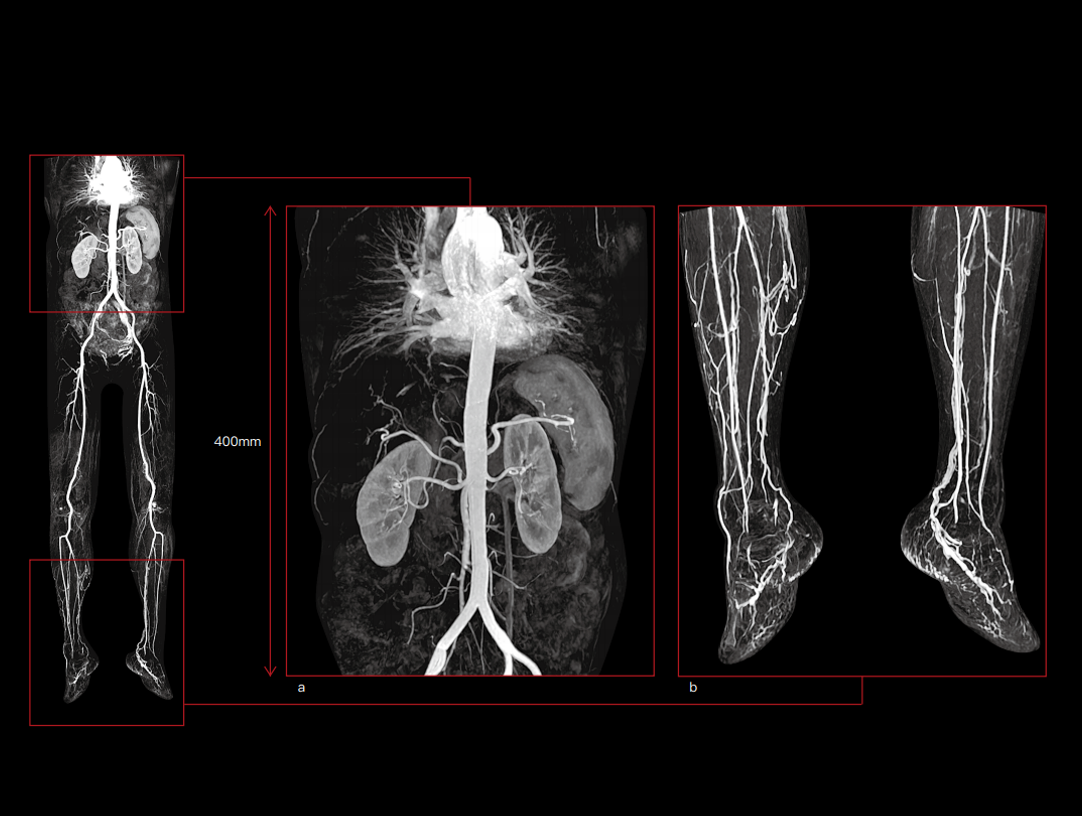

The powerful 3.0T magnet uses a 170 cm short-magnet design to ensure high homogeneity of the magnetic field, which provides a solid foundation for fast imaging and excellent fat saturation over a large FOV, as well as outstanding off-center imaging.